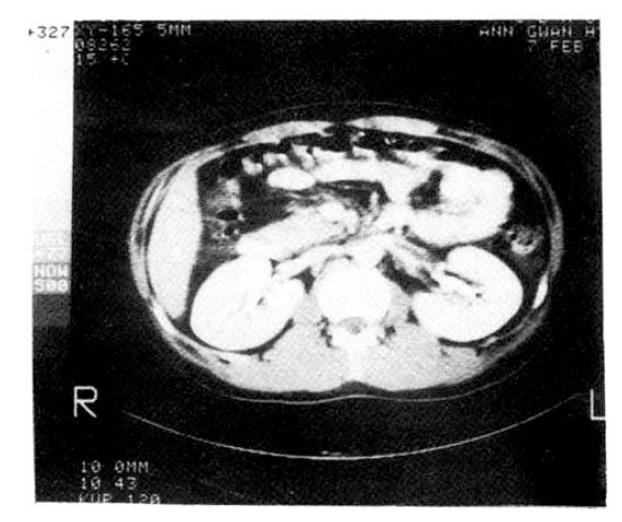

The coexistence of nephrotic syndrome and renal vein thrombosis has been of medical interest since Rayer’s description in 1840. Renal vein thrombosis has been underdiagnosed because of its variable clinical and radiological findings but it becomes a more frequently recognizable clinical entity since diagnosis can be easily established by modern angiographic techniques. Generally it has been believed that renal vein thrombosis may cause nephrotic syndrome. But recent articles strongly suggest that renal vein thrombosis is a complication of the nephrotic syndrome rather than a cause. We report three cases of nephrotic syndrome associated with renal vein thrombosis.